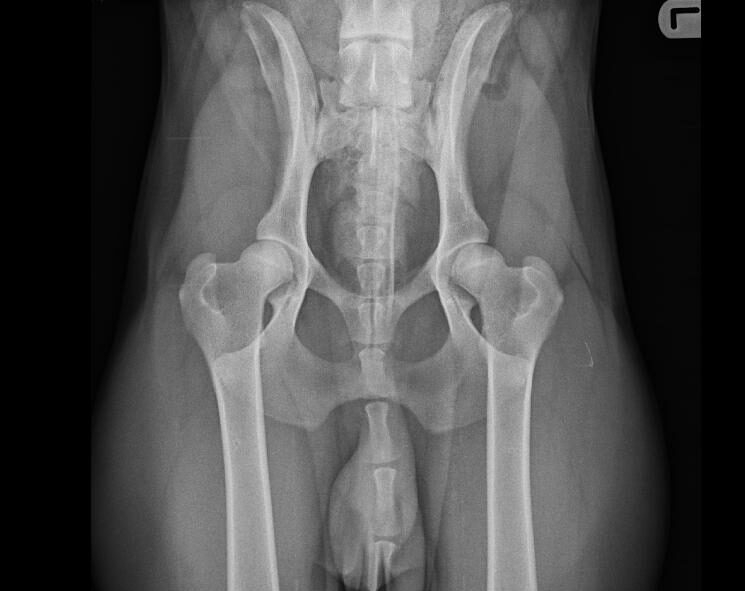

Bij een röntgenfoto wordt er met behulp van röntgenstralingen een opname gemaakt van de binnenkant van het lichaam. Bepaalde weefsels in het lichaam houden de röntgenstralen tegen, terwijl andere ze gemakkelijk doorlaten. Hierdoor is het mogelijk om verschillende structuren in het lichaam op een röntgenfoto te zien.

Röntgenfoto’s kunnen worden gebruikt om verschillende aandoeningen en problemen te helpen diagnosticeren, variërend van botbreuken tot problemen met interne organen zoals de longen, lever en nieren. Ook worden röntgenfoto’s gebruikt voor het maken van officiële HD/ED-röntgenfoto’s voor het beoordelen van de heup- en ellebooggewrichten bij bepaalde hondenrassen.